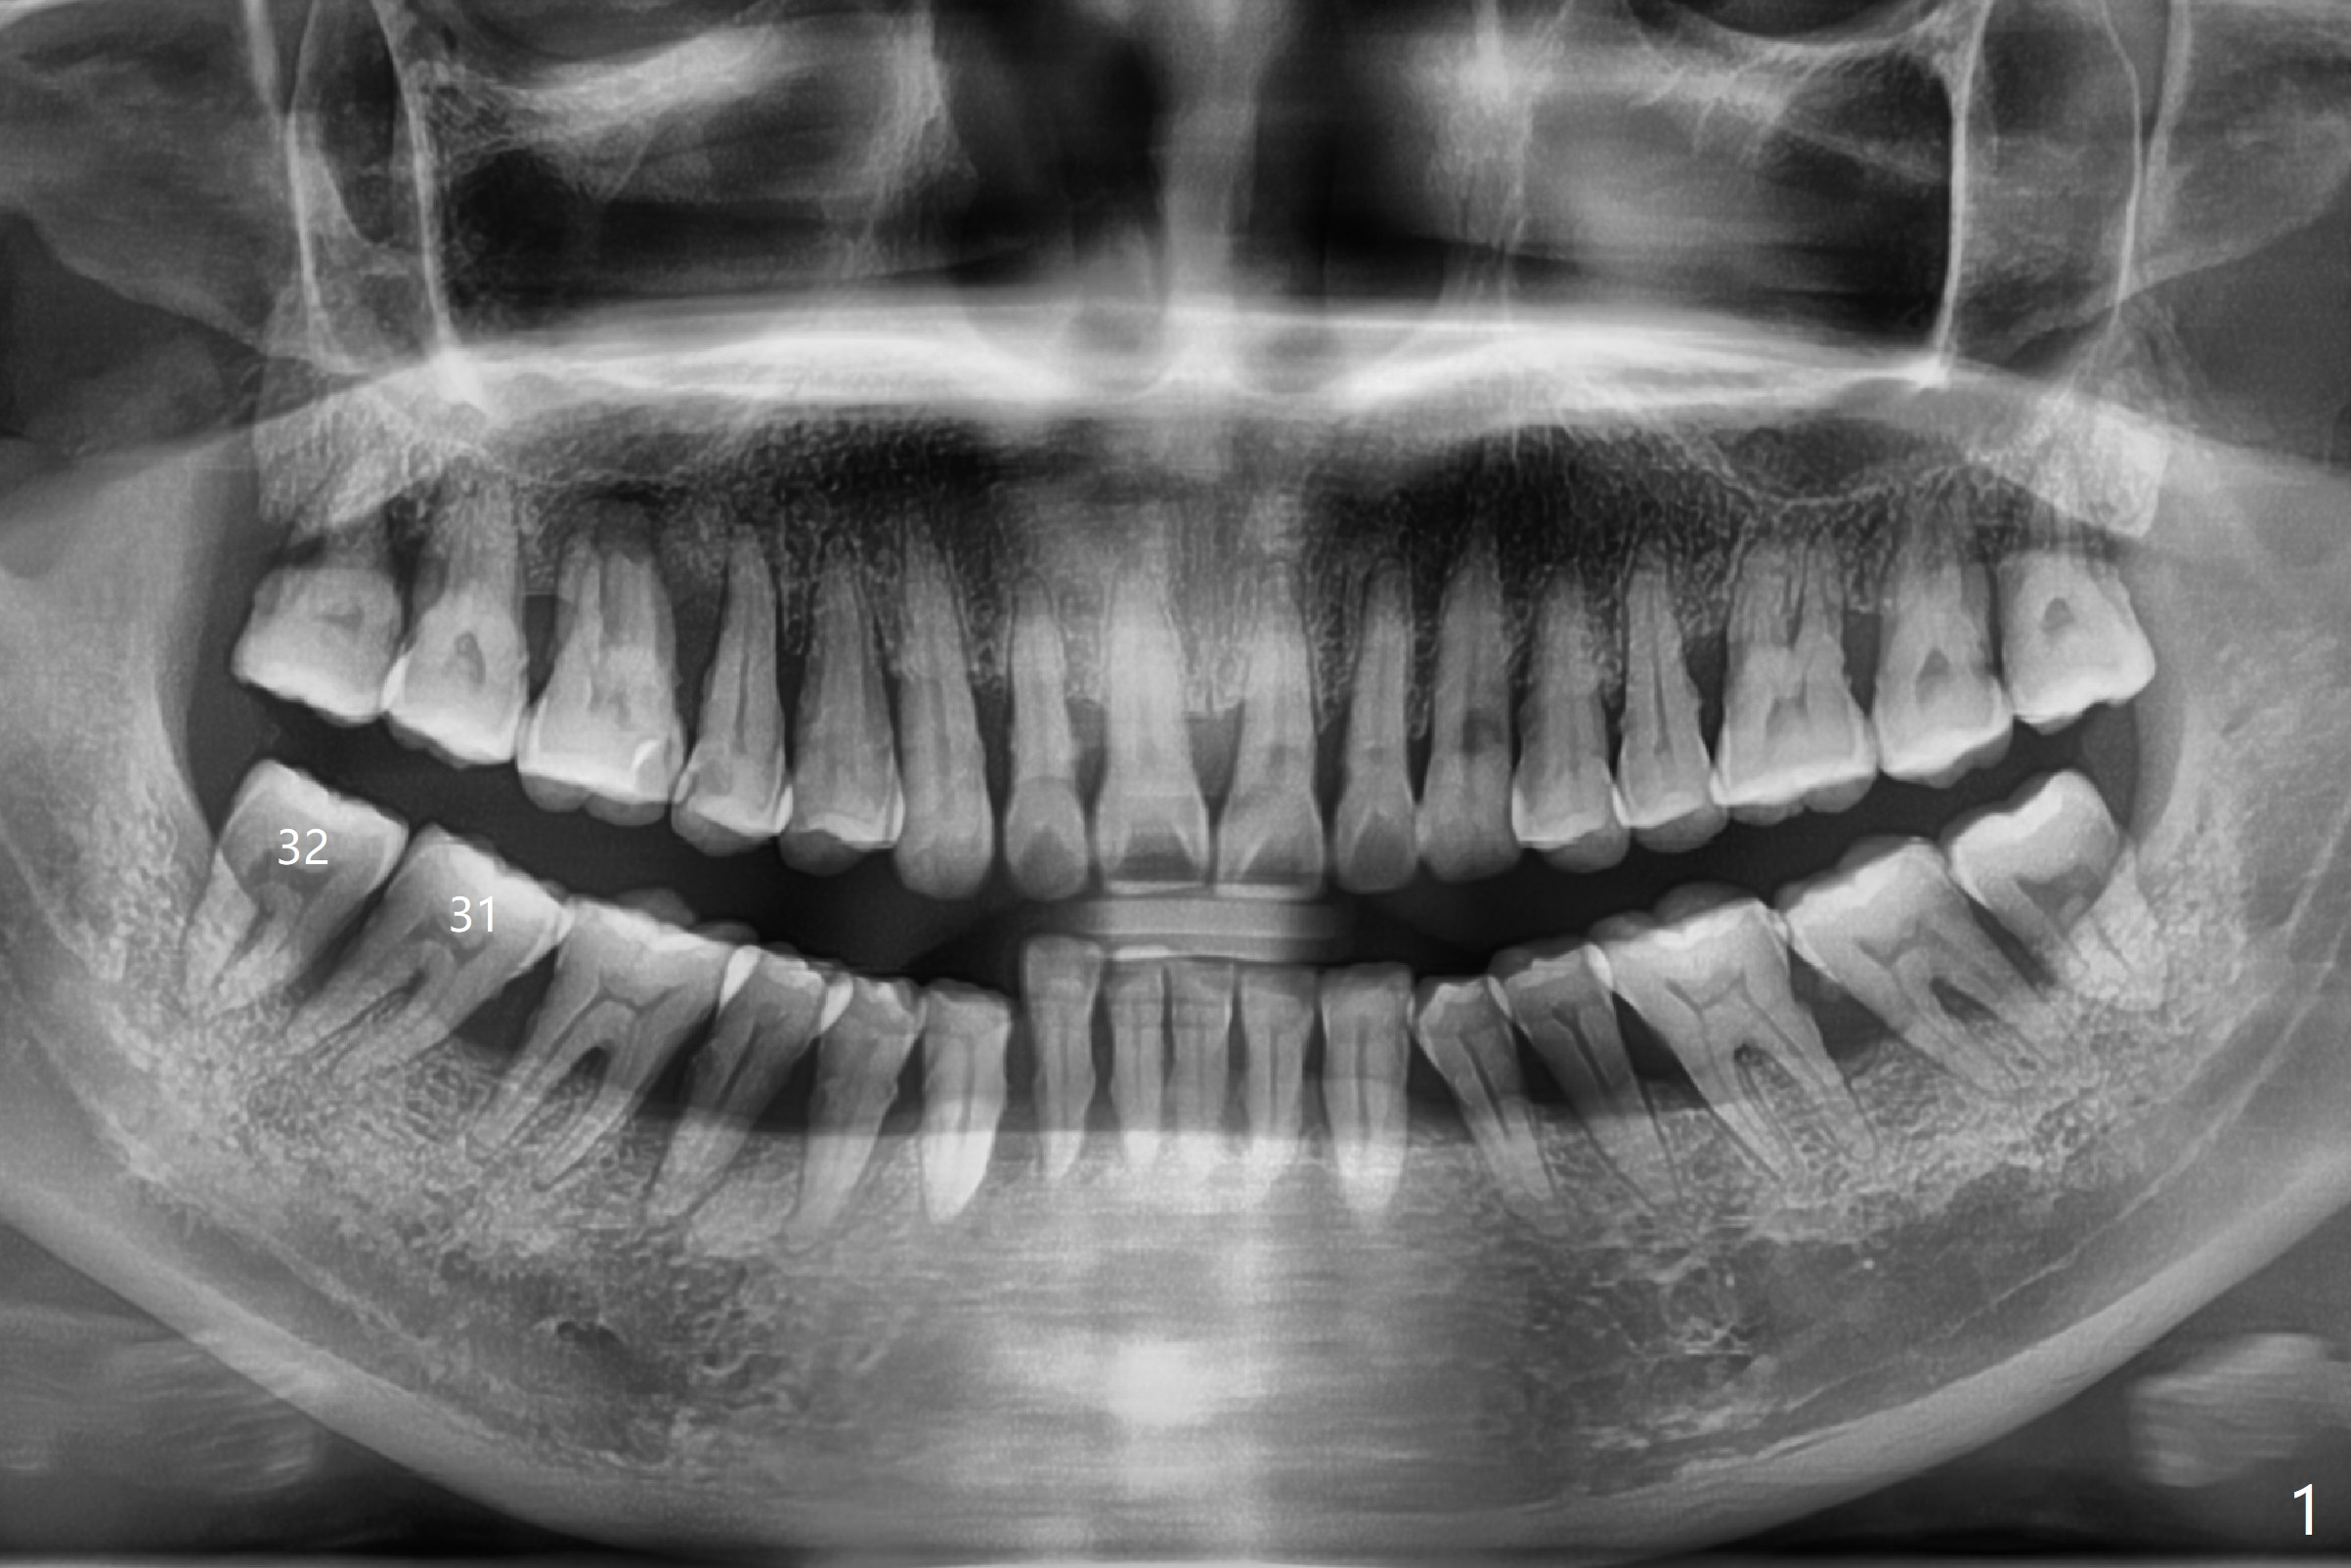

Socket Preservation at Lower 3rd Molar

with Severe Bone Loss

A 44-year-old woman (YHM) has generalized moderate localized severe chronic periodontitis (Fig.1). Periodontal abscess develops between the teeth #31 and 32. Since the pain and mobility is more severe at #32 than 31, the former is extracted (Fig.2). After thorough curettage and copious irrigation, Osteogen plug is placed in the distal portion of the socket (Fig.3, 4 O), while allograft in the mesial one (B), with collagen plug on the top (C) before suturing (Fig.5). The tooth #31 is stable and pain-free with formation of new bone distal 7 months postop (Fig.6,6' *), while bone loss at #3 and 4 is more severe.